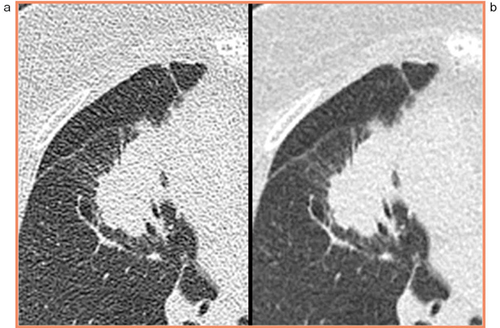

さて,2つ目の話題として,昨今取り上げられることの多い逐次近似再構成法AIDR 3Dがある。AIDR 3Dを使用することで,胸部CTでどの程度画質が向上し,被ばく線量の低減が図れるかについて,ACTIve Studyでも研究を進めてきた。2011年末より研究を開始し,2012年のRSNAで私が発表した,胸部CTにおけるAIDR 3Dの効果に関して報告する。この研究では,事前に綿密に検討した上で,標準線量相当としてまず240mA(84mAs),その半分の120mA(42mAs),さらにその半分の60mA(21mAs)の3つの線量を設定した。それぞれの患者をこの線量設定で3回撮影し,それぞれのデータをAIDR 3Dありとなしの二通りで画像化すると,6パターンの画像が得られることになる。6パターンのCT画像を全員分集めた上でランダム化し,3名の読影者が上・中・下肺野と4パターンの肺病変の画質を採点した。結果としては,(1)「240 mA・AIDR 3Dあり」が全採点項目で最も高得点,(2)「120 mA・AIDR 3Dあり」は「240 mA・AIDR 3Dなし」より高得点または同点,(3)「60 mA・AIDR 3Dあり」は「120 mA・AIDR 3Dなし」より高得点または同点,ということになった。すなわち,AIDR 3Dは画質を向上させるだけではなく,50%程度の大幅な線量削減を可能にするだろう,というデータを得ることができた。この結果は,種々の補足解析を加えた上で,近いうちに論文として発表する予定である(図1)。

図1 60mA(21mAs)で撮影された肺腫瘍の画像

a:AIDR 3Dなし,b:AIDR 3Dあり